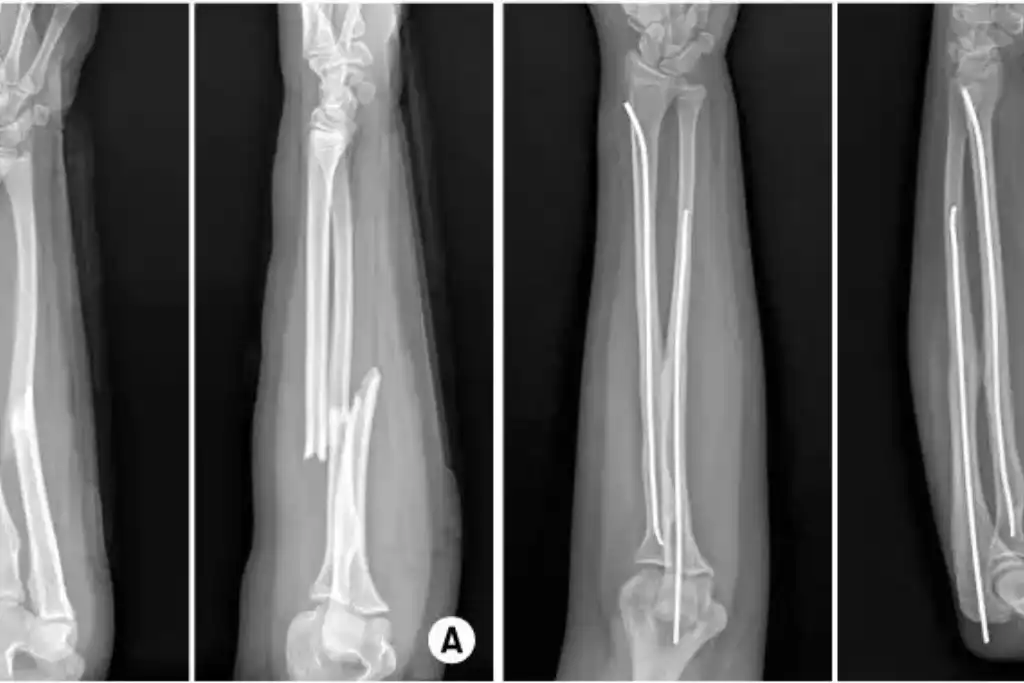

Before & After

Orthopedic Surgery Results